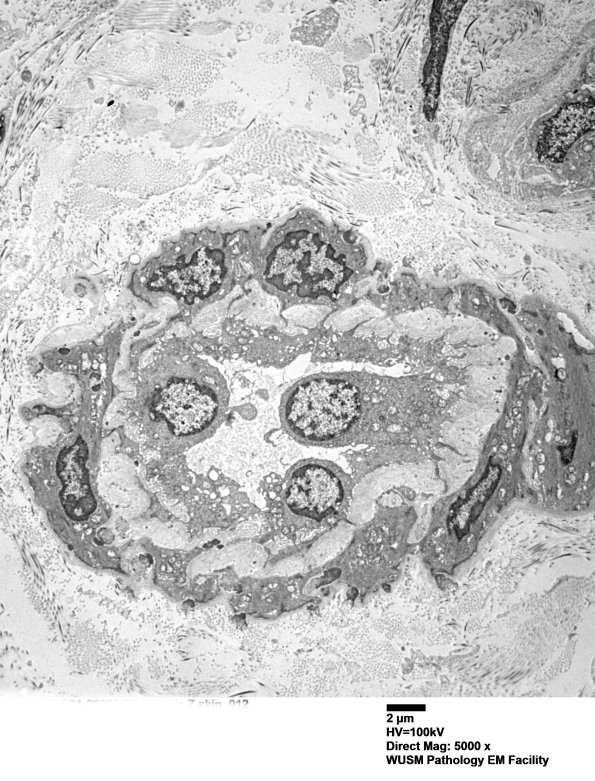

11E5A A microvessel with prominent endothelia and smooth muscle cells which appear atrophic. (electron micrograph)